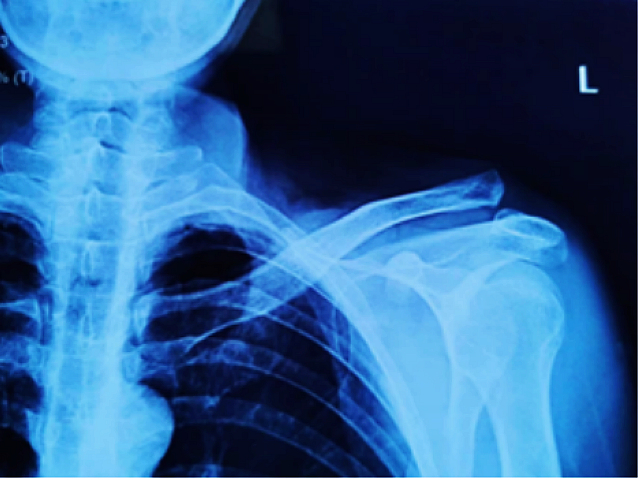

该患者因外伤致左肩部疼痛、活动受限,左肩锁关节压痛明显,肩关节活动受限,琴键征(+)。入院后检查提示,左肩锁关节脱位(RockwoodⅢ型)。

术前影像